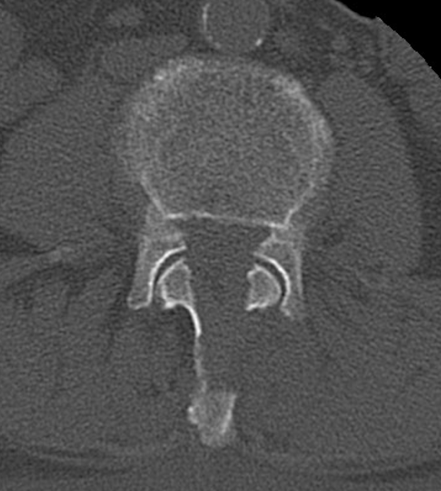

- 脊髄造影(ミエログラフィー)CT(図2)

造影検査を行うことで、CT検査でも狭窄部位の確認ができます。

図2:第4/5腰椎間で造影剤の途絶を認める。